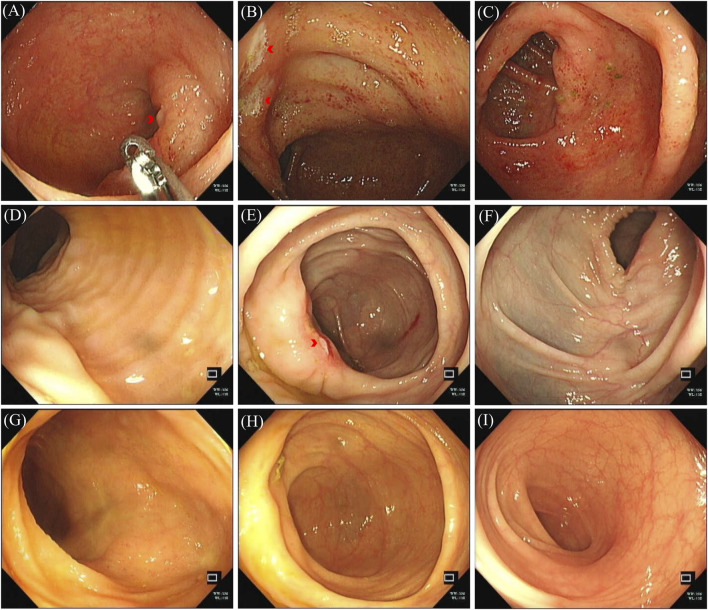

Case presentation: We report the case of a 62-year-old woman with NSCLC and brain metastases, who tested positive for ALK. She had been treated with Alectinib for nearly 4 years. The patient experienced diarrhea for 4 days, and a subsequent colonoscopy revealed pancolitis along with multiple ulcers in the terminal ileum and ileocecal valve. Given the severity of these symptoms, classified as a grade 3 adverse event by the Common Terminology Criteria for Adverse Events (CTCAE), Alectinib was discontinued. Treatment with oral enteric-coated Mesalazine tablets led to a resolution of the diarrhea and a significant improvement in the pancolitis and ulcers upon follow-up. The patient's anticancer therapy was subsequently switched to Ceritinib capsules. At follow-up, she demonstrated a stable tumor condition with no recurrence of intestinal ulcers or colitis.